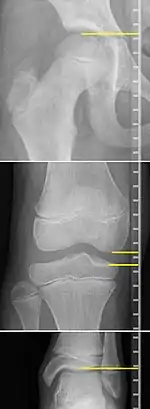

On X-rays, there is generally measurement of both the femur and the tibia, as well as both combined.[4] Various measuring points for these have been suggested, but a functional method is to measure the distances between joint surfaces:[4]

- Femur length: The superior aspect of the femoral head and the distal portion of the medial femoral condyle.

- Tibial length: The medial tibial plateau and the tibial plafond

- Orthoroentgenogram, which takes separate images of the hip, knee and ankle.

On X-rays, the length of the lower limb can be measured from the proximal end of femoral head to the center of the plafond of the distal tibia.[11]